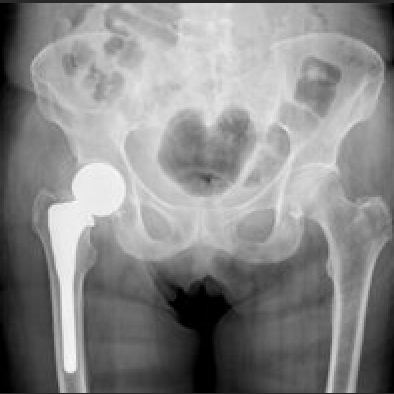

• It is most likely related to muscle soreness or arthritic changes in the hip joint.

Read my blog article if you want to learn more about hip fracture prevention. I have also written a blog post on hip protectors.